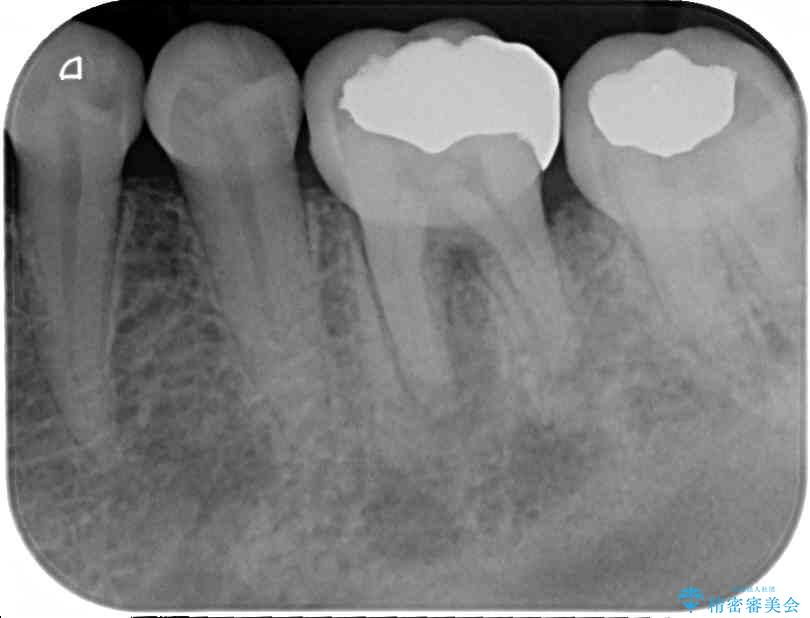

以前むし歯治療をした後から定期的に痛むことがあるとのことで、レントゲン写真より神経組織が失活していることが予想されました。

銀歯を外すと神経組織の一部が取り除かれており、歯根に付け根に穴が空けられている状態でした。

出血の原因は以前の治療で空けられた穴であると考え、封鎖をするとともに根管治療を行い、その後オールセラミッククラウンにて補綴治療を行うこととしました。

術後6ヶ月でレントゲン写真を撮影したところ、出血の原因であった穴付近の溶けていた骨が回復している様子が認められました。

• むし歯で歯茎から血が出てくる オールセラミッククラウンでの補綴治療 治療前画像